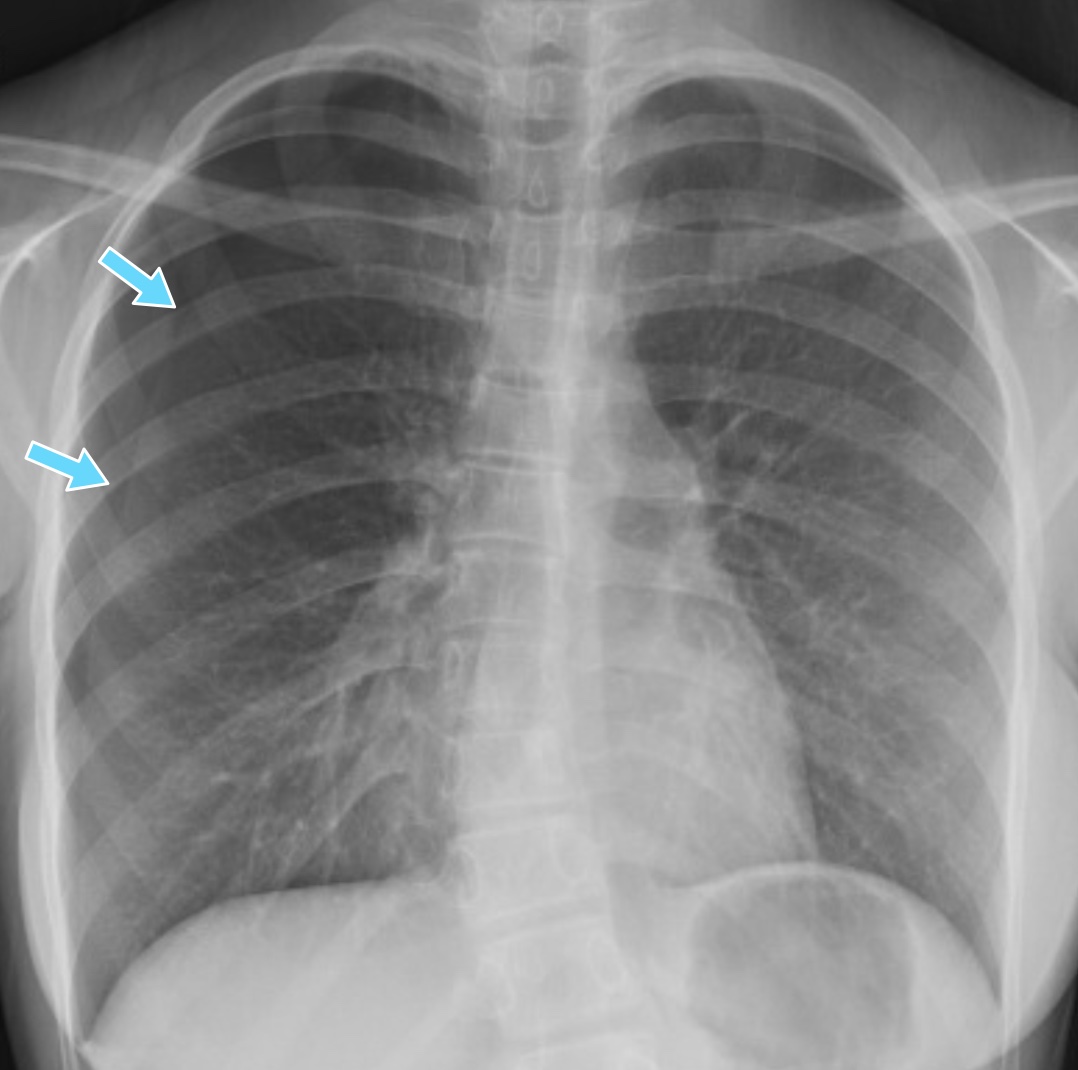

What's the diagnosis? By Dr. Abby Renko EM Daily Sharp Pain In Chest When Breathing Right Side It can also sometimes indicate an. Web possible causes of right sided chest pain include an injury, acid reflux, a heart or lung problem, and an infection,. Web the right side of the chest is home to the right lung, the right side of the heart, and the esophagus. Chest pain is scary, and it can be serious. But a. Sharp Pain In Chest When Breathing Right Side.